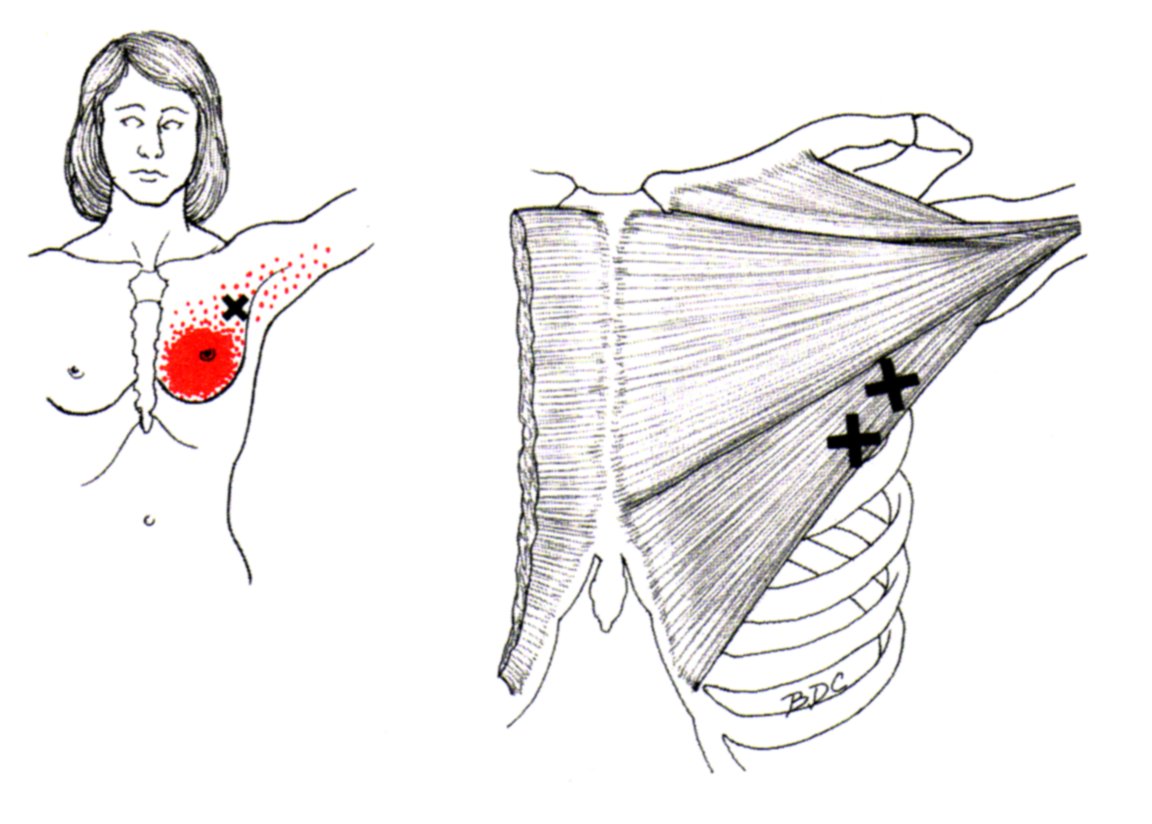

육.트리거 포인트

통증 유발점은 통증과 불편함을 유발하는 근육 긴장 또는 과사용 영역입니다. 대흉근도 예외는 아니며 신체의 다른 부분에 통증을 유발하는 통증유발점을 만들 수 있습니다.

대흉근의 통증유발점은 일반적으로 흉골에 부착되는 근육의 흉골 부분에 있습니다. 이러한 통증유발점은 가슴, 어깨, 팔에 통증과 불편함을 유발할 수 있습니다.

통증 유발점이 대흉근에 있을 때 신체의 다른 곳에서 느낄 수 있는 연관통을 유발합니다. 통증은 어깨, 팔 또는 손으로 퍼질 수 있습니다.

대흉근의 통증유발점은 과도한 사용, 부상, 잘못된 자세 등 다양한 요인으로 인해 발생할 수 있습니다. 통증유발점 마사지, 스트레칭, 근력운동 등으로 치료할 수 있습니다. 더 이상의 통증과 불편함을 유발하지 않도록 대흉근 통증유발점에 대한 치료를 찾는 것이 중요합니다.